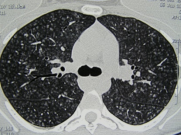

病例:男,48岁,接触钴酸锂5.5年。治疗前胸部HRCT,显示双肺磨玻璃影,以及马赛克影:

ero为什么不显示叶俏教授:HRCT是发现和鉴别「过敏性肺炎」的重要环节,何种表现指向预后不良?使患者发病的危害因素躲在哪些环境中?_https://www.jmylbn.com_新闻资讯_第47张

脱离暴露和糖皮质激素3月后,胸部HRCT较前改善:

ero为什么不显示叶俏教授:HRCT是发现和鉴别「过敏性肺炎」的重要环节,何种表现指向预后不良?使患者发病的危害因素躲在哪些环境中?_https://www.jmylbn.com_新闻资讯_第48张